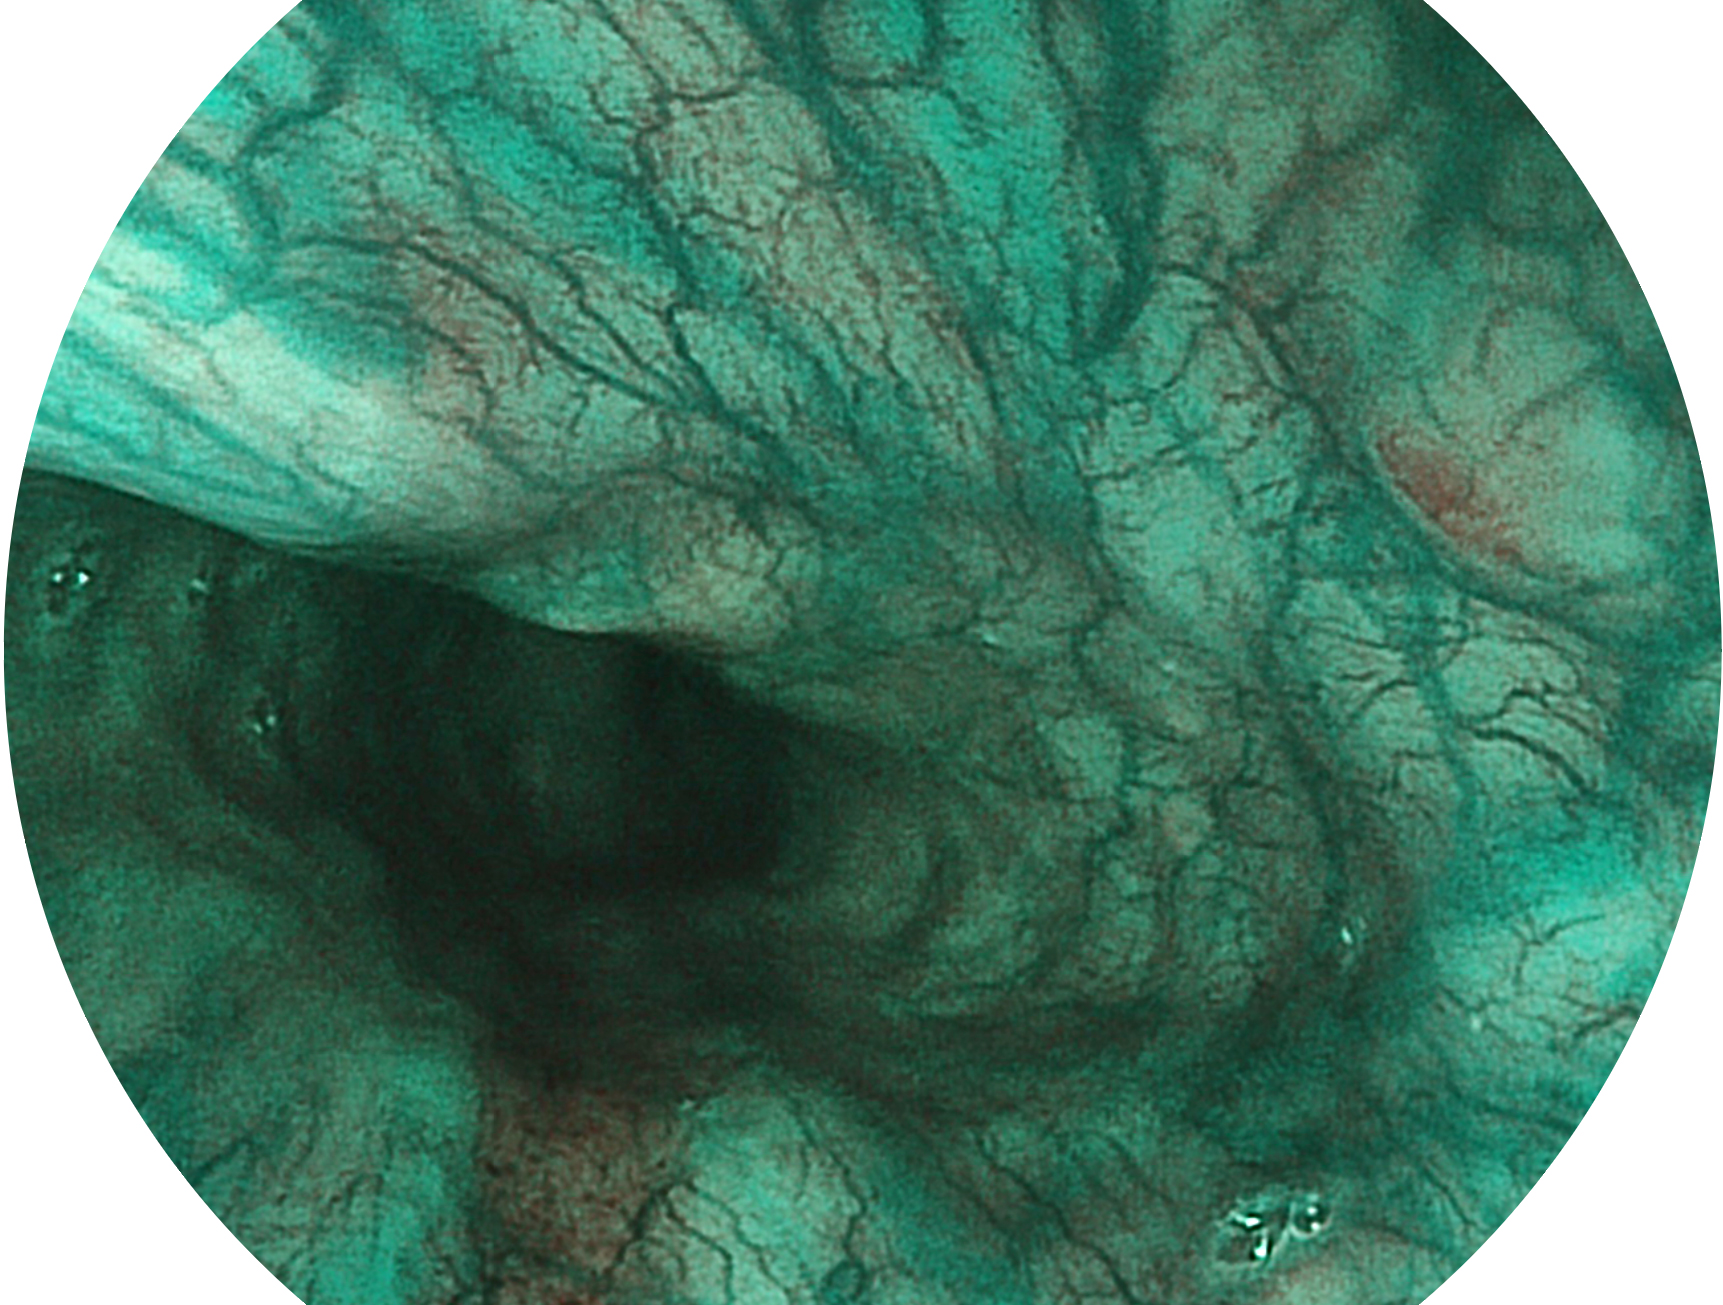

云顶集团官网新开发的内镜染色技术,主要是基于多波长LED 光源的开发,VLS-55Q 四波长LED 光源是由四个不同颜色的LED光按照相应照明模式所规定的特定发光比例进行合束后形成,合束后形成的照明光的光谱由红光、绿光、蓝光及蓝紫光这四个不同的波段范围构成。具有更高光谱自由度,通过光谱比例的控制,实现了聚谱成像技术,英文全称为“Spectral Focused Imaging, SFI”,缩写为“SFI”和光电复合染色成像技术,英文全称为“Versatile Intelligent Staining Technology, VIST”,缩写为“VIST”。